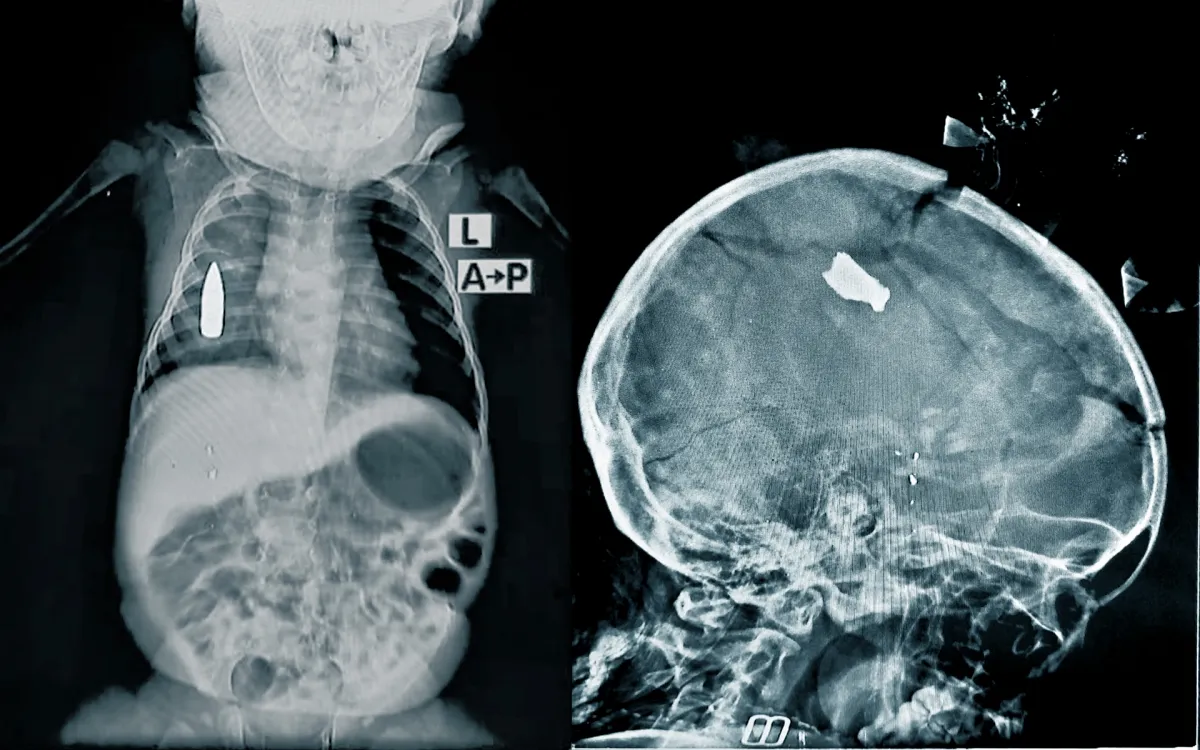

Röntgenbilder zeigen schwere Verletzungen bei Kindern: eine Kugel im Körper des 18 Monate alten Jungen und einen Granatsplitter im Kopf des 20 Monate alten Mädchens.

„Riyad, ein 18 Monate altes Baby, wurde in die Notaufnahme gebracht, nachdem eine verirrte Kugel seine rechte Seite getroffen hatte, während er schlief“, berichtet Dr. Moeen*, Leiter des medizinischen Teams von Ärzte ohne Grenzen. „Unser Team kämpfte vier Stunden lang um Riyads Leben. Aufgrund des massiven Blutverlustes lag die Überlebenschance bei nur 50 Prozent.“ Die Blutung konnte gestoppt werden, jedoch blieb die Kugel in der Brust des Kindes. Eine Operation ist derzeit nicht möglich, da dem Krankenhaus die notwendigen chirurgischen Kapazitäten fehlen.